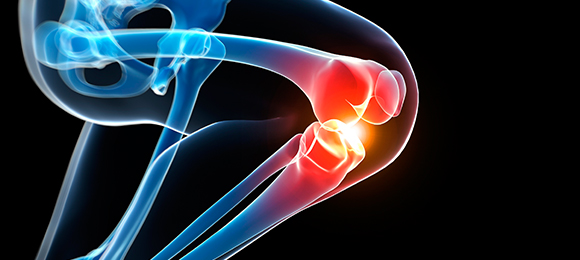

좁아진 신경 통로에 풍선 카테터를 넣어 공간을 넓히고 약물을 주입해,

다리 통증과 저림을 줄이는 최소침습 척추 시술입니다.

가느다란 카테터를 경막외 공간에 넣어 목(경추)·허리(요추) 신경 주변 유착과 염증을 풀어주고,

통증을 완화하는 최소침습 척추 시술입니다.

허리디스크나 척추관협착증 치료에 사용되는 최소 침습 수술 방법입니다.

피부에 작은 절개(약 7mm)를 통해 내시경과 기구를 넣어 병변을

직접 보면서 디스크만 선택적으로 제거합니다.